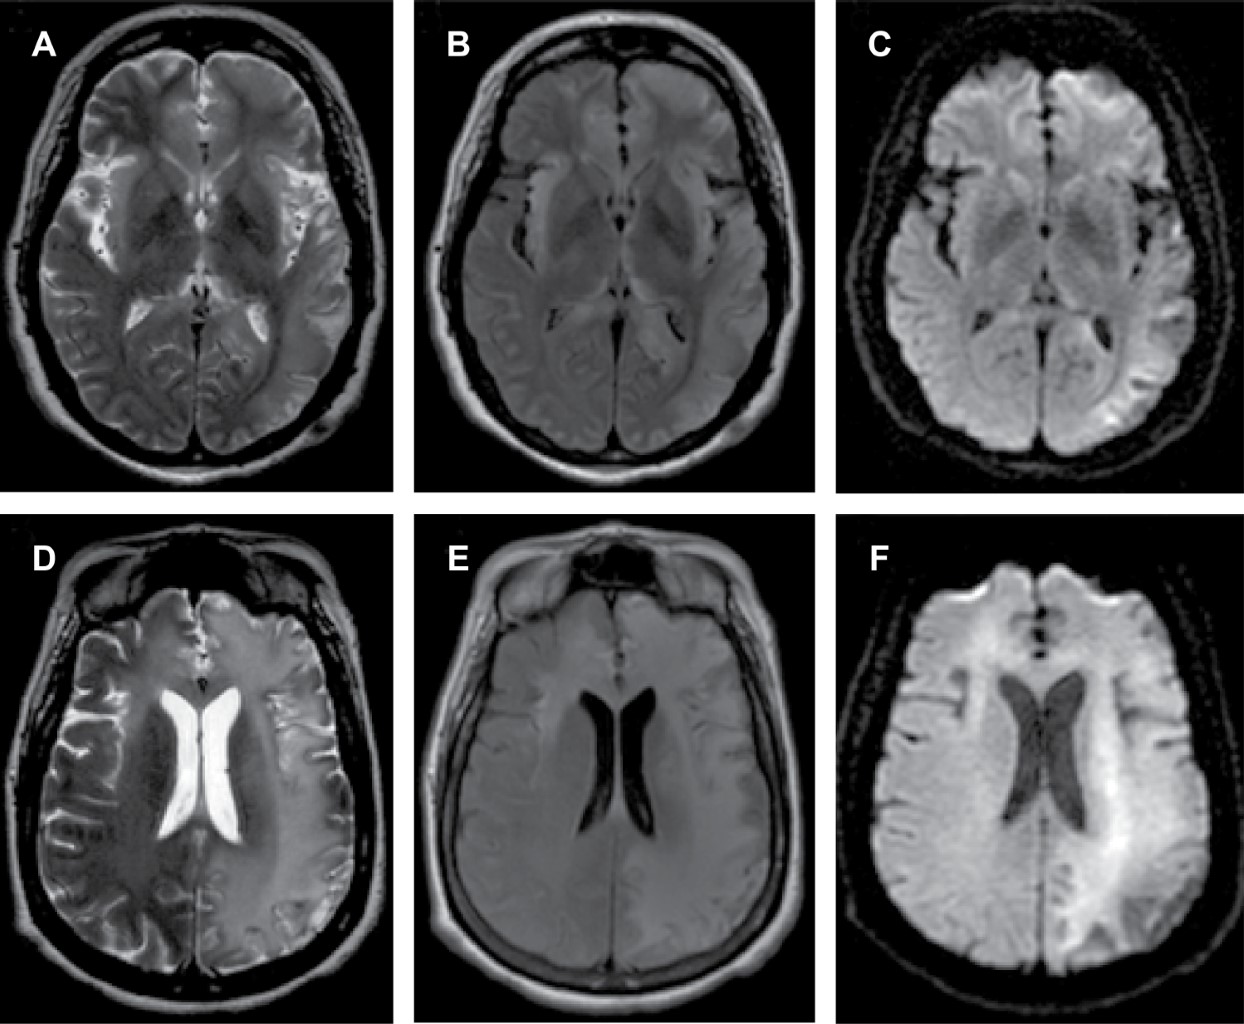

Herpes simplex encephalitis

Figure 1